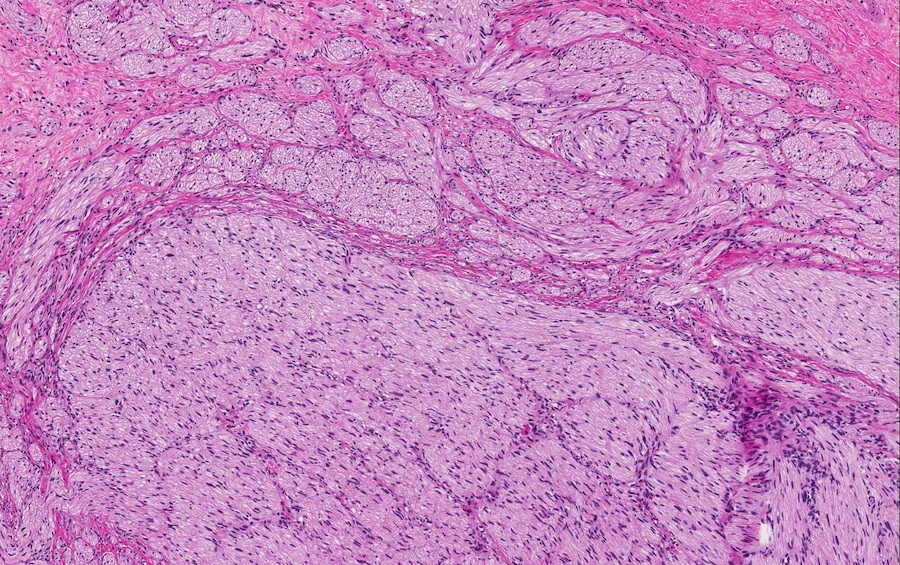

Microscopic images:

Microscopic images:

Both cases showed disorganized and thickened nerve bundles composed of spindle shaped cells, without atypia. Case A also showed a focal foreign body type giant cell reaction adjacent to the disorganized nerve bundles and a strongly immunoreactive S100 stain.

Histology typically shows hyperplastic nerve bundles, positive for S100.

Microscopic images:

Microscopic images:

Both cases showed disorganized and thickened nerve bundles composed of spindle shaped cells, without atypia. Case A also showed a focal foreign body type giant cell reaction adjacent to the disorganized nerve bundles and a strongly immunoreactive S100 stain.

Histology typically shows hyperplastic nerve bundles, positive for S100.